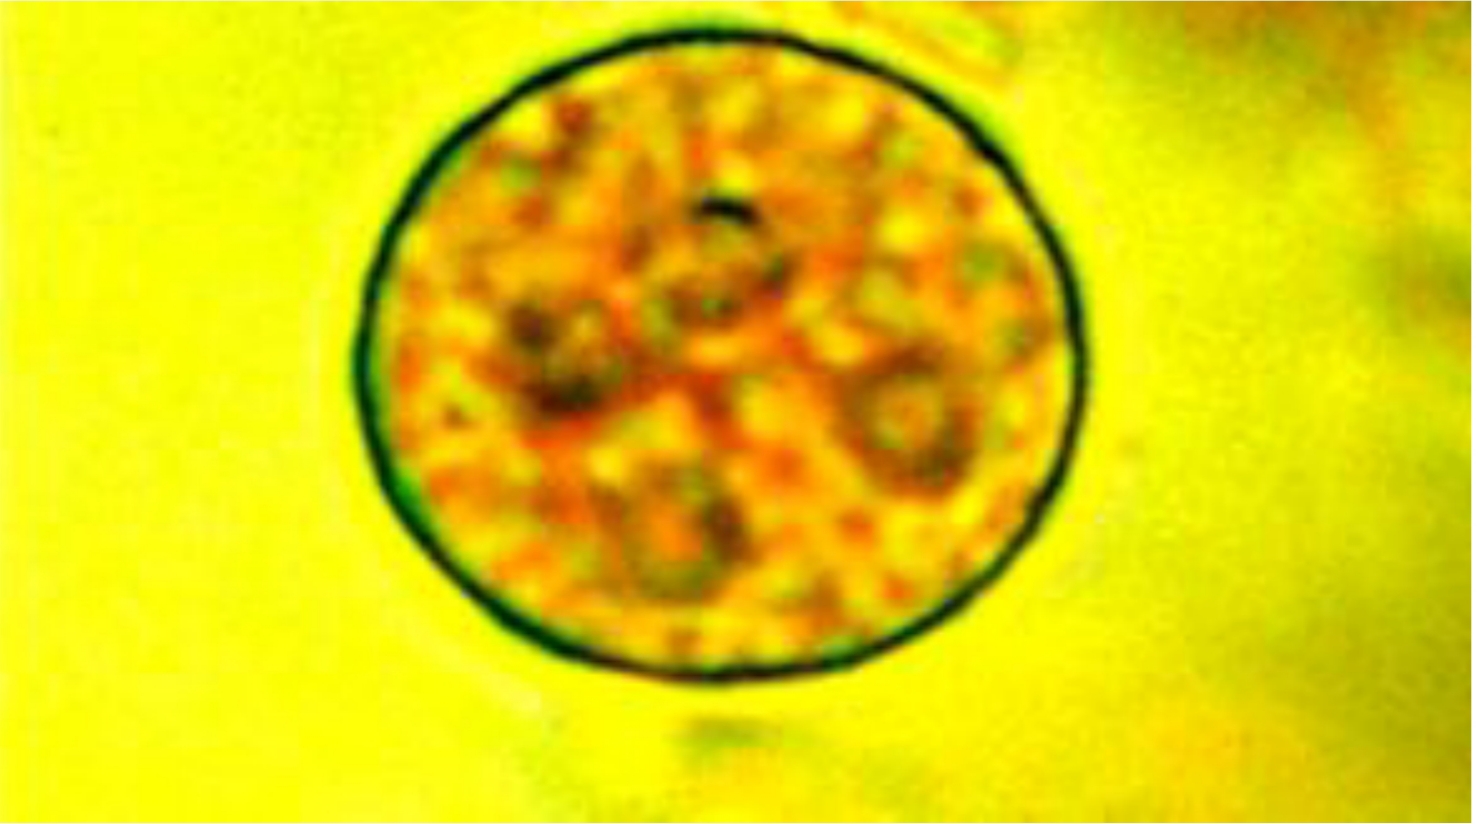

Mature quadrinucleated cyst of Entamoeba histolytica